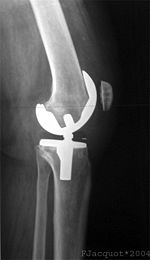

جراحة إستبدال الركبة يمكن أن تكون إستبدالا جزئياً أو إستبدال الركبة بالكامل.[2] في الإستبدال بصفة عامة تتكون من جراحة استبدال الأسطح المريضة أو التالفة للركبة بأجزاء معدنية أو بلاستيكية على شكل مكونات تسمح باستمرار حركة الركبة.

من خلال الجراحة يتم استئصال أسطح المفصل المصاب واستبدالها بمفصل صناعي. ويمكن أن تؤدي هذه الجراحة إلى تخفيف الألم وتحسين الحركة في مفصل الركبة.

بعد اجراء تعقيم شامل لمنطقة العملية، يتم احداث شق بطول 8-12 سم في الجزء الأمامي من الركبة. عند كشف الحيز في مفصل الركبة، يقوم الجراح باخراج الأنسجة الغضروفية والعظمية الزائدة، التي تؤثر سلباً على الحيز في مفصل الركبة.[5]

لاحقا، يتم تعديل أسطح المفصل بحيث تستطيع احتواء المفصل الاصطناعي المركب من البلاستيك والمعدن. يتم الصاق المفصل الاصطناعي بعظمة الفخذ، الساق والرضفة، بواسطة مادة ملاطية أو مادة أخرى، تستعمل كمادة لاصقة فسيولوجية. من ثم، يتم تثبيت المفصل الاصطناعي إلى عضلات الركبة والأربطة الداعمة للمفصل، من أجل الحصول على أداء حركي في المفصل بشكل مماثل للوضع الطبيعي. يتكون الجزء الملتصق بعظمة الفخذ من معدن صلب وأملس، والذي يستطيع تحمل أوزان ثقيلة. يتم تغطية المفصل بضمادة مرنة.